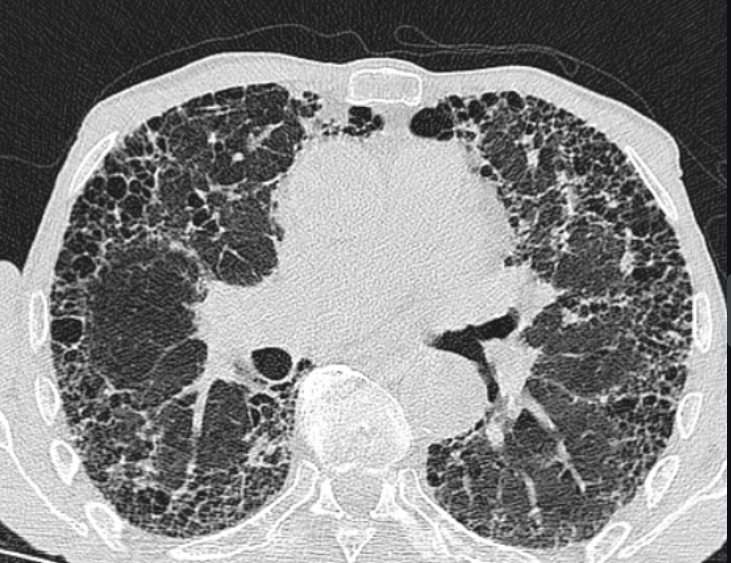

Features of Definite UIP

A

Subpleural and basal predominant

Heterogenous

Honeycombing

+- bronchiectasis

Features of Probable UIP

+- mild GGO

but no honeycombing